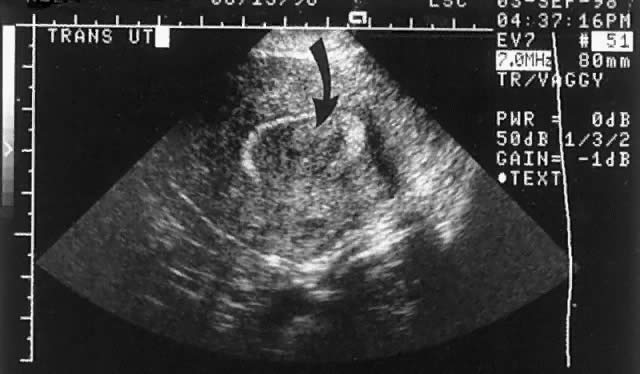

The advantage of transvaginal imaging of the endometrium was rapidly appreciated by the radiologic community in the mid-1980s.16 Fedele, in a frequently quoted series, found transvaginal scanning without infusion had a sensitivity of 100% and a specificity of 94% for the detection of submucous leiomyomas.17 Series by Cincinelli and colleagues and by Narayan and Goswamy found slightly lower sensitivities at 90% and 94%, respectively.18,19 Narayan and Goswamy scanned patients in their infertility group at three points during the menstrual cycle. This allowed the investigators to take advantage of the varying endometrial echo-architecture (Figs. 6 and 7). Towbin and associates found that office hysteroscopy and transvaginal scanning without infusion were only 79% and 53% sensitive, respectively, in identifying space-occupying lesions of uterine cavity among 65 patients who underwent hysterectomy or operative hysteroscopy. The investigators thought the decreased sensitivity resulted from residents in training performing the diagnostic studies rather than experts in the field.20

Fig. 6. A densely echogenic submucous leiomyoma (curved arrow) is seen disrupting a proliferative phase endometrium (straight arrow).